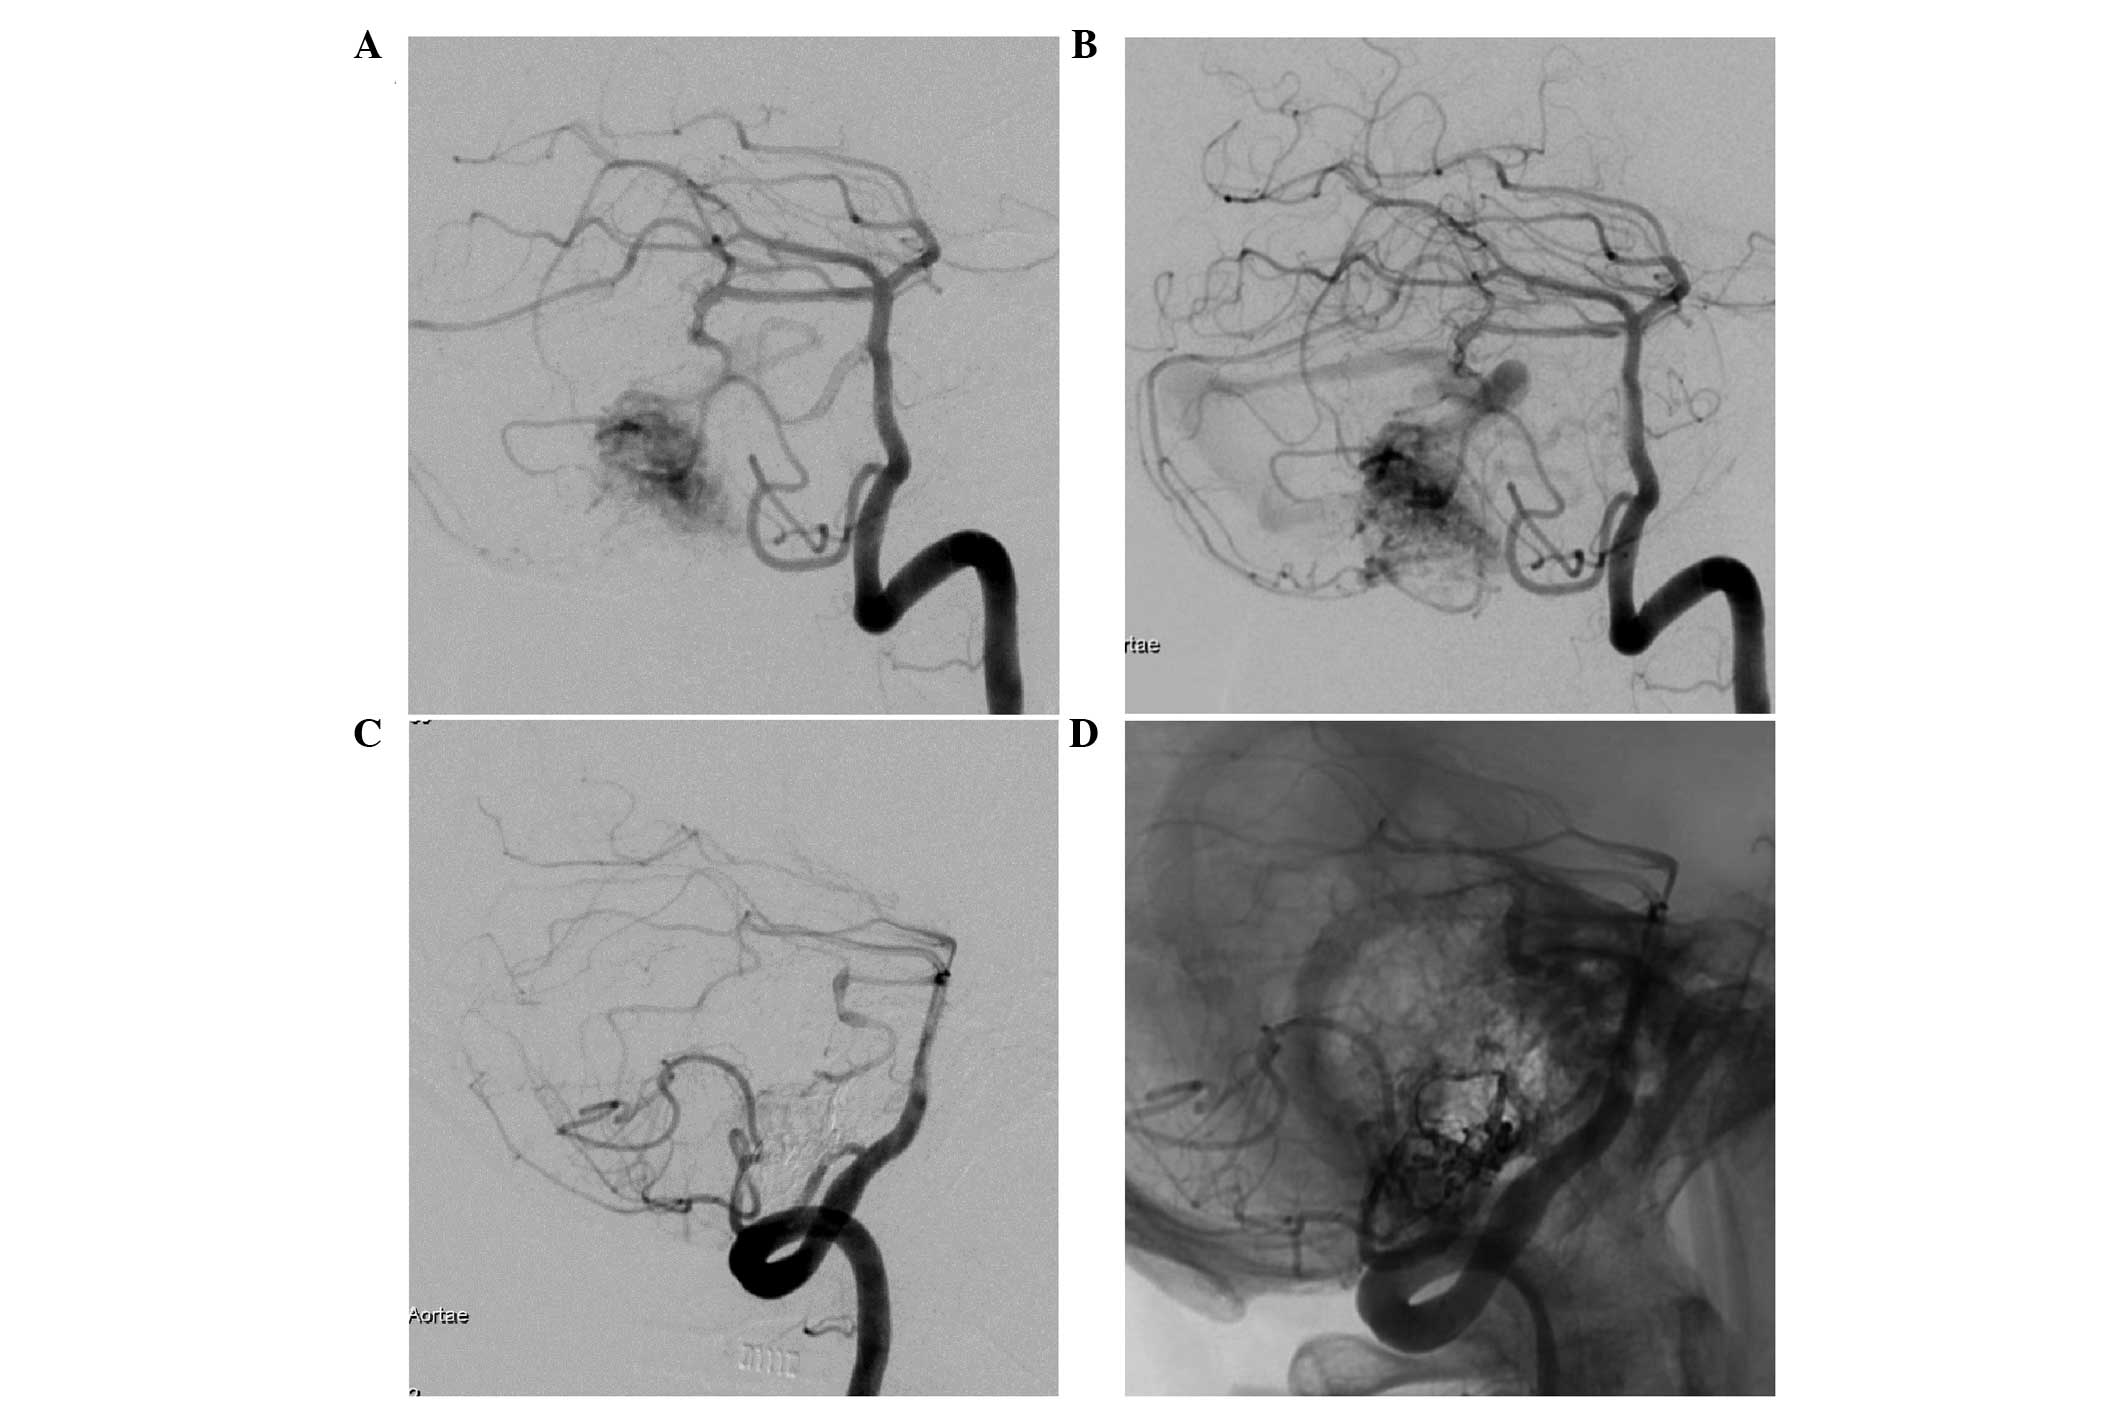

A 32-year-old male was admitted to the First Hospital of Jilin University (Changchun, China) on December 6, 2014, suffering from recurrent pain in his right cheek for two years, which had increased in severity over the previous 6 months. The patient reported that the pain began three years previously as a stabbing-like, intense pain that occurred suddenly on the right lower lip and mandible without any prior signs; each episode of pain lasted for 10–30 sec. The first period of pain lasted ~1 week and was self-relieved without medication. The pain recurred following a period of 6 months, and the duration of each episode of pain extended to 2–3 min. The patient was administered 800 mg oral carbamazepine (Novartis, Basel, Switzerland) daily, which was effective at relieving the pain on the right side of the face of the patient. In the 6 months prior to hospital admission, the frequency of the pain in the right cheek of the patient increased. The pain occurred >6 times every day and each episode lasted 10–30 min, and daily oral administration of 1,200 mg carbamazepine was not effective at controlling the pain. Clinical examination demonstrated that no significant trigger point could be palpated and there were no abnormalities in corneal reflexes or facial sensation. Subsequent magnetic resonance imaging (MRI) demonstrated the presence of flow-void signals in the abnormal vessels in the right CPA (Fig. 1). Digital subtraction angiography (DSA) further confirmed the diagnosis of bAVMs, and demonstrated that the malformed niduses were fed by the right SCA and the AICA, and drained into the adjacent venous sinuses on the same side (Fig. 2). Although the patient only exhibited symptoms of TGN, the patient was treated with interventional embolization, due to the risk that the bAVMs may bleed in the future. Embolization was conducted under general anesthesia with intravenous 0.05–0.1 mg/kg midazolam (Nhwa, Jiangsu, China), 1.0–1.5 µg/kg remifentanil (Renfu, Yichang, China), 0.2–0.3 mg/kg etomidate (Nhwa), 0.6 mg/kg rocuronium (Organon, Brussels, Belgium), and was maintained with 0.6 mg/kg propofol (Nhwa), 5–10 mg/(kg/h) and 0.1–0.2 µg/(kg/min) remifentanil (Renfu, Yichang, China). Following arterial puncture and sheath insertion in the femoral artery using the Seldinger technique (13), a 6F-guiding catheter (Cordis Co., Miami, FL, USA) was inserted into the left vertebral artery. Under the guidance of a Mirage micro-wire (ev3, Irvine, California, USA), a Marathon micro-catheter was inserted into the bAVMs. The micro-catheter entered the bAVMs via the right AICA and onyx-18 glue (ev3) was slowly injected. Onyx-18 glue diffused well in the bAVMs and embolized the majority of the malformations. Angiography was conducted immediately following surgery, which demonstrated that the majority of the bAVMs had disappeared and the draining veins were patent (Fig. 2). There were no complications following the surgical procedure and the pain in the right cheek of the patient was completely relieved one week following the surgical procedure. The patient was satisfied with the outcome of the embolization surgery. Post-surgical follow-ups were conducted for a period of two years via telephone. The patient experienced no further pain in his right cheek, and thus chose not to return to the hospital for a follow-up reexamination. The present study was approved by the Ethics Committee of the First Hospital of Jilin University and patient informed consent was obtained prior to the study.